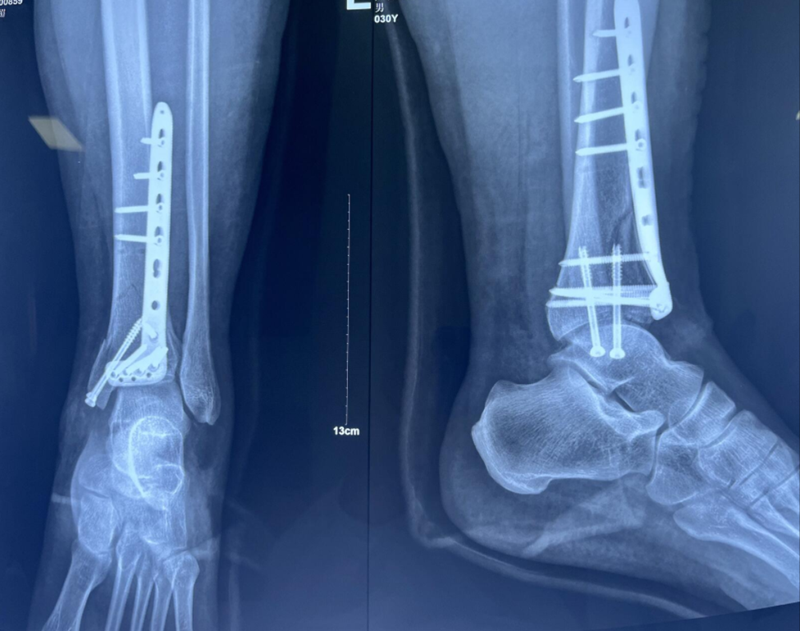

术后影像学资料:

六、小结

Reudi-Allgower固定四步骤

1、腓骨切开复位固定。

2、胫骨远端关节面解剖复位固定。

3、重新组装的胫骨远端关节面用解剖板与胫骨干连接。

4、骨移植。